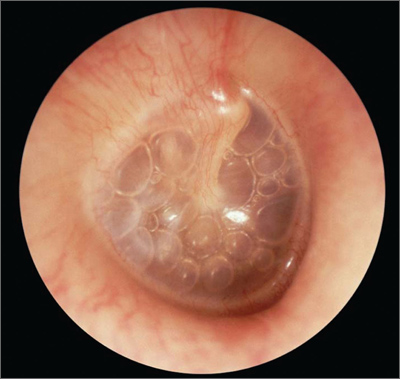

Otitis Media with Effusion

Tympanic membrane is retracted with prominence of handle of malleus which is more horizontal

Tympanic membrane may be bulging or have air fluid level behind

Yellow/amber appearance

Light reflex apparent